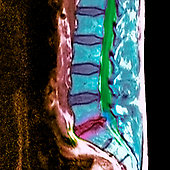

سکته مغزی آسیب عصبی حاد ناشی از اختلال خونرسانی به قسمتی از بافت مغز که ناشی از انسداد رگ مغزی به وسیله یک لخته خونی و یا پارگی یکی از عروق تغذیه کننده آن قسمت بافت مغز میباشد.